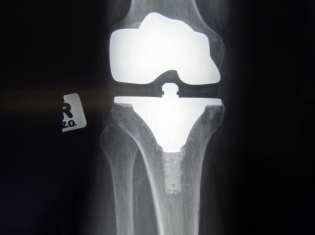

(RxWiki News) One goal of knee replacement surgery for arthritis patients is to improve mobility and pain, but in many cases, pain after surgery presents a new issue for these patients.

Researchers behind two new studies wanted to explore postoperative pain in knee replacement patients and search for risk factors associated with pain after surgery.

These studies found that gender, age, weight and certain surgical factors were all associated with a greater risk for postoperative pain. Women, middle-aged adults and the obese were all more likely to have severe pain after a knee replacement.